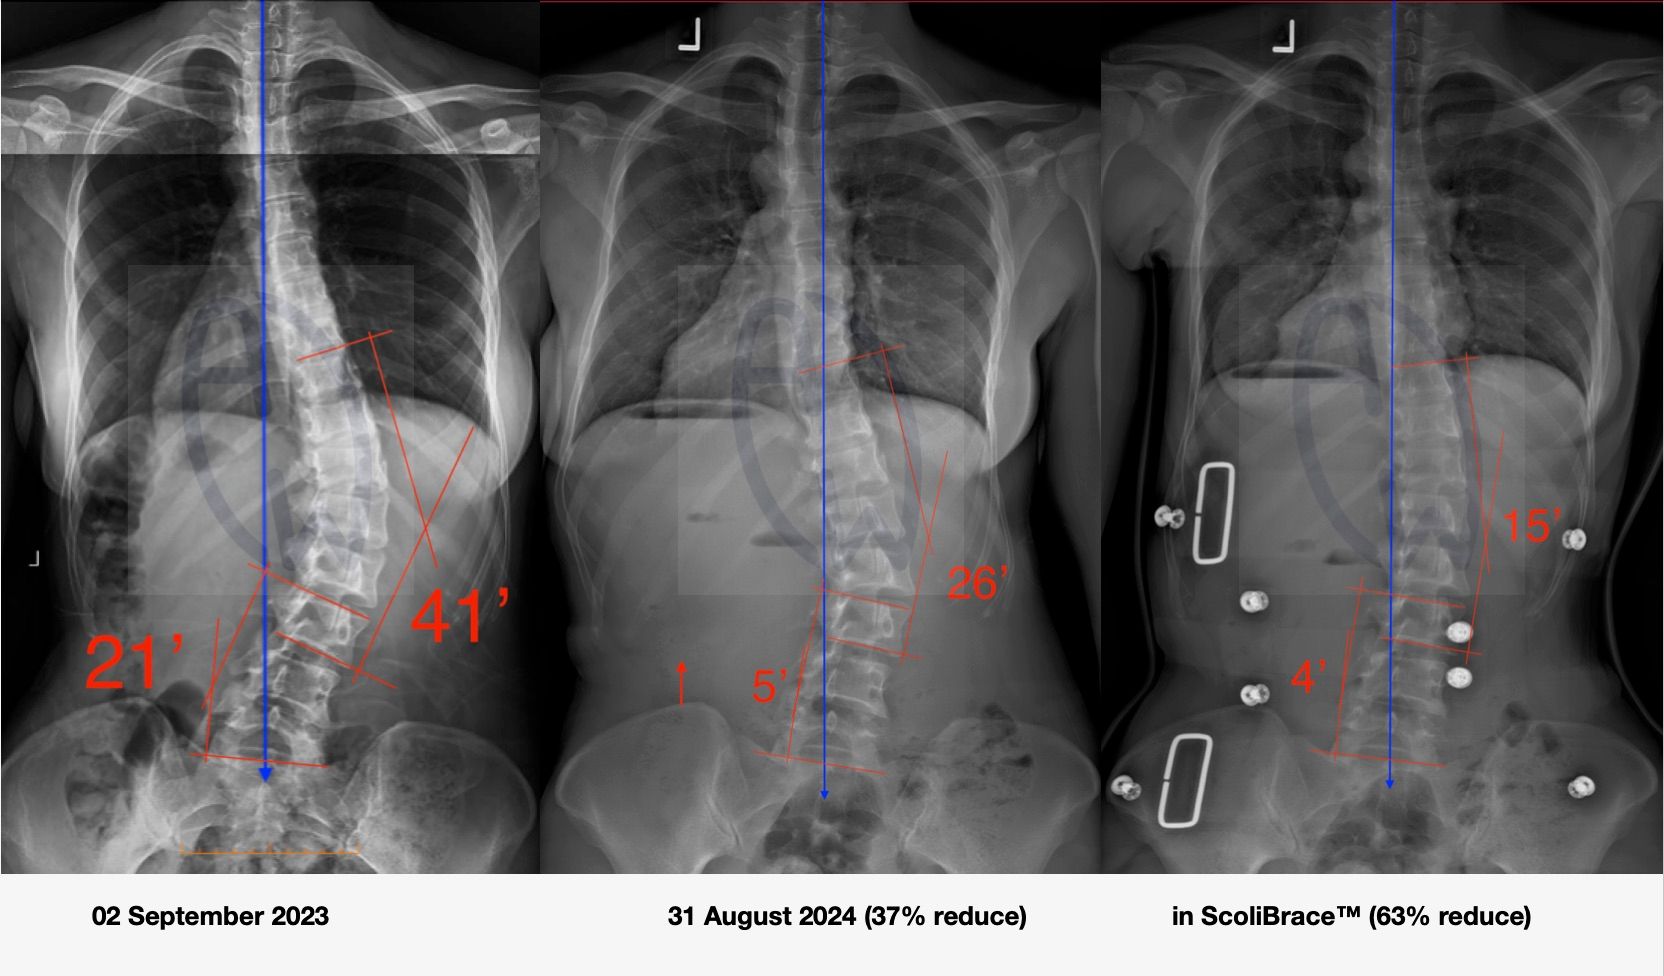

xray comparison.JPG

The image is shared for educational purposes with patient consent. Individual outcomes vary. Structural correction does not automatically restore full respiratory function. Clinical assessment is required.